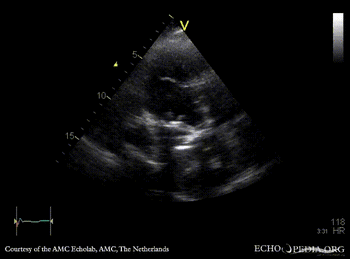

Case 108